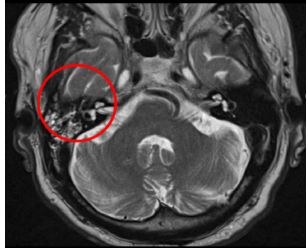

Qué estudio diagnostica el colesteatoma y cuál es la mejor pista

A

TC Y RM

Pista: Masa que destruye el hueso

Enfermedad que con la secuencia en T2 tipo DWi se muesta una lesión hipertensa

neoplasia del tejido epidérmico que crece en el interior del conducto auditivo, es una complicación de otomastoiditis

Clínica del colesteatoma

Dolor retroauricular

Sordera

Meningitis

a la EF masa blanquecina en el oido

Destruye hueso y cadena osicular